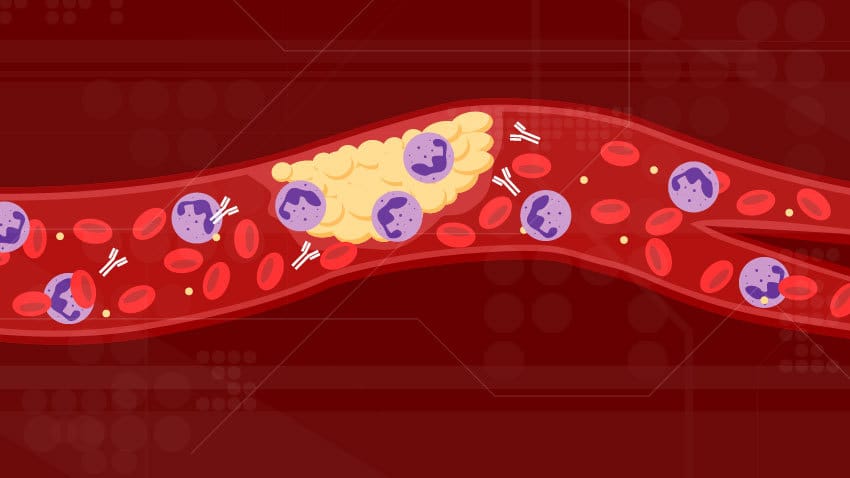

قد تكون أعداد الحالات والوفيات في إنخفاض، لكن الأخبار التي تفيد بأن لقاح أسترازنكا AstraZeneca قد تم ربطه بحالات ( جلطات دموية نادرة ) وتم تعليق إستخدامه لدى الشباب في ألمانيا وهولندا يعد تطورًا مزعجًا.

في هذه الحالة، أثيرت مخاوف من أن اللقاح قد يكون مرتبطًا بسبع وفيات من بين ما مجموعه ٣٠ حالة نادرة ( لتخثر الدم )، ظهرت بعد إعطاء اللقاح.

كما أنه ليس من الواضح وجود علاقة سببية بين لقاح أسترازنكا AstraZeneca والجلطات ( ومعظمها مجموعة متنوعة تسمى التخثر الوريدي للجيوب الأنفية الدماغية ، CSVT).

ومع ذلك، حتى في حالة وجود مثل هذا السبب، يجب أن نلاحظ أنه من بين تأثيرات فيروس كورونا العديدة ، يتم تضمين ( موضوع التخثر ).

بشكل حاسم، فإن فرص الإصابة بجلطة من خلال الإصابة بفيروس كورونا هي أكثر إحتمالا بعدة مرات من فرص الإصابة على جلطة من اللقاح.